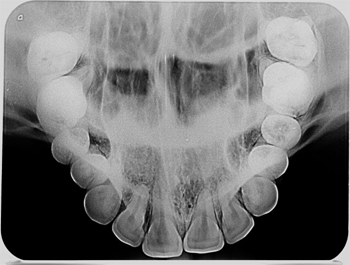

Ortho X - Radiografia Oclusal

É utilizada como complementação de exame para delimitação e localização de áreas patológicas de maxila e mandíbula tais como : dentes inclusos, dentes supranumerários, cistos, lesões, torus, extensão de fendas palatinas e disjunção palatal em ortodôntia.